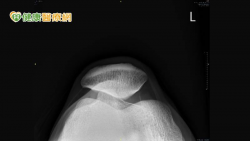

健身膝蓋痛!小心是髕骨股骨疼痛症候群惹的禍 - 健康醫療網 - 健康養生新聞資訊網路媒體

2022-03-09 11:00:00 by 健康醫療網 @ 健康醫療網 [引用來源]

髕骨又被稱為膝蓋骨,是一塊位於膝蓋前面的小骨頭,髕骨會藉由肌腱及韌帶與這塊大腿股骨及小腿脛骨相連接。若是因為膝蓋在活動時,髕骨有不正常滑動,造成髕骨與下面的股骨軟骨產生摩擦,進一步造成膝蓋周圍深處疼痛,這就是髕骨股骨疼痛症候群(Patellofemoral pain syndrome),又稱作髕骨外翻或髕骨軟化。尤其在跑步、上下樓梯或蹲下等膝蓋彎曲角度較大時,疼痛情形會較明顯。 什麼原...... [閱讀更多]